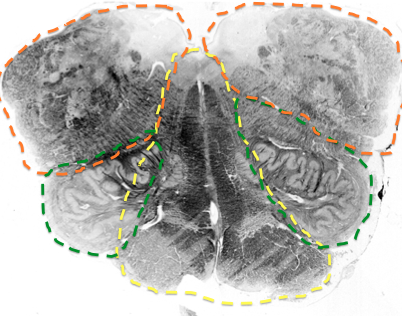

what supplies rostral medial medulla? until when?

paramedian branches of basilar. once you get to the mouse ears

replaced by paramedian branches of basilar

when does AICA first appear?

in rostral medulla when CN 8 comes in

in the medulla it just supples dorsal cochlear nucleus and the CN 8

What does AICA supply? until when?

AICA

lateral part of middle pons until the rostral pons section

purple

superior cerebellar artery

supplies the superior cerebellar peduncle area throughout the pons